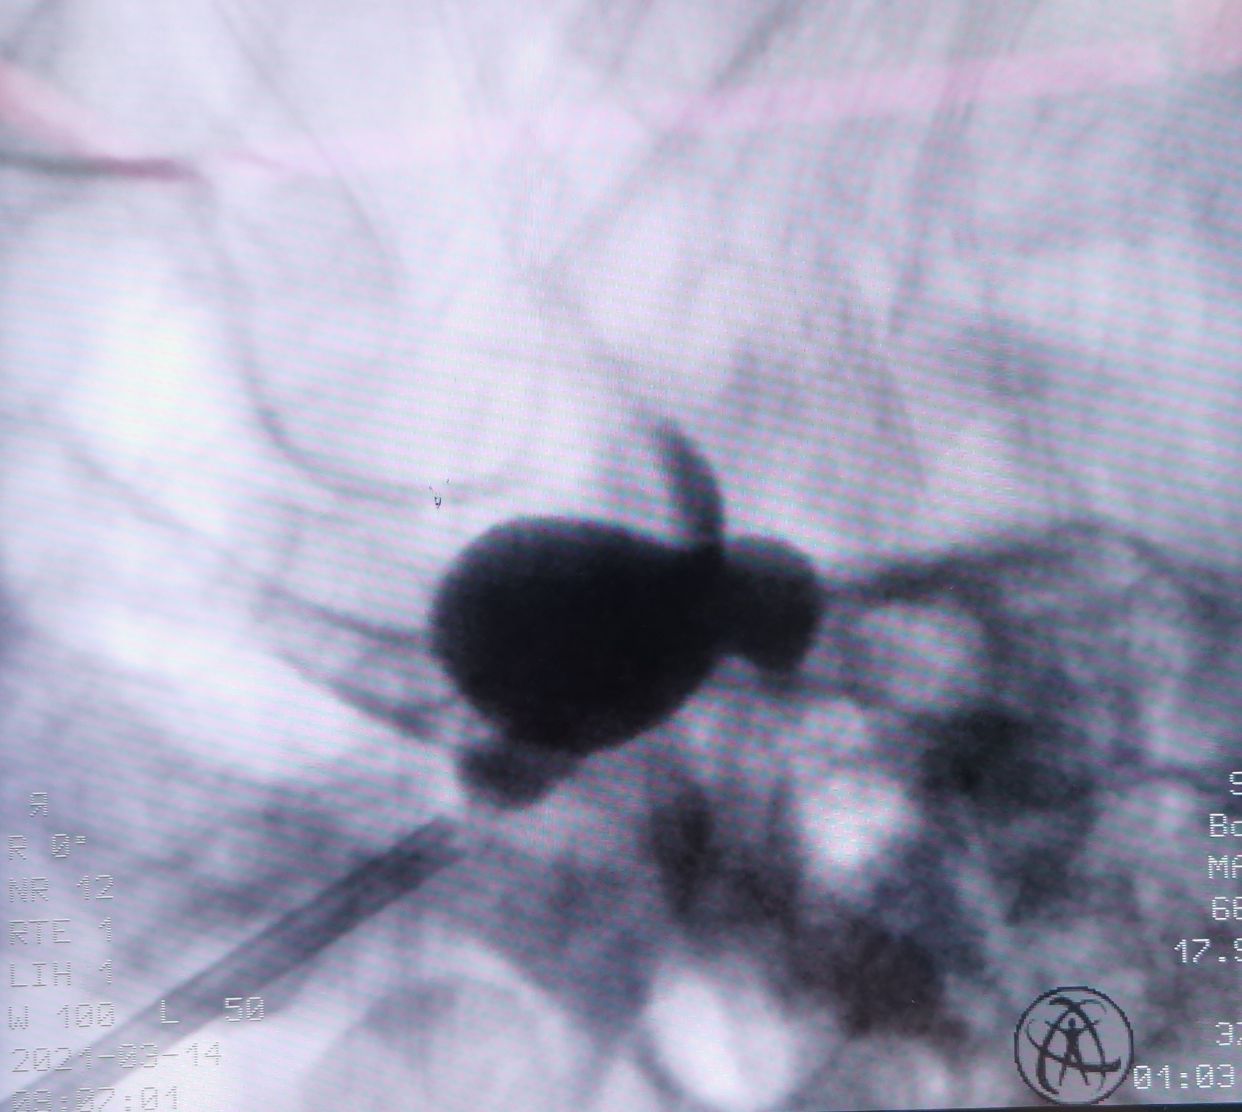

穿刺针到此,无法进入,骨质完全遮挡

改为中入路

成功